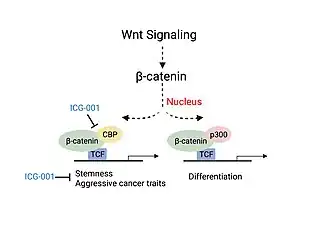

For example, CBP alone has been implicated in a wide variety of pathophysiologies including colorectal cancer as well as head and neck squamous cell carcinoma. In these diseases, association of CBP with β-catenin has been shown to promote cancer cell proliferation and disease aggressiveness, whereas p300/ β-catenin leads to cell differentiation and/ or apoptosis.[11][13] CBP has also been shown to help modulate liver function via maintenance of energy homeostasis in response to changes in cell nutrition conditions by regulating the activity of transcription factors and genes responsible for lipogenesis and gluconeogenesis.[6] CBP is also implicated in the etiologies of several other diseases including hematologic malignancies and other solid tumors, diabetes, schizophrenia, Alzheimer's disease, depression, and many other neurological conditions.[14][15][16][17][18]

Colorectal cancer and head and neck cancer (HNSCC) disease severity have been linked to the association of CBP with β-catenin, a critical factor involved in the canonical Wnt signaling pathway.[11][13] Association of CBP with β-catenin leads to the transcription of genes responsible for more aggressive cancer traits including the presence of cancer stem cell populations, decreased immune cell infiltration and likelihood of metastasis.[13] Experiments studying the use of a small molecule inhibitor of β-catenin/CBP association (ICG-001), that does not block p300/β-catenin association, saw decreased carcinogenesis and increased cellular differentiation and apoptosis.[11][13]